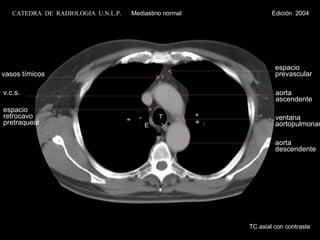

T v.c.s. espacio  retrocavo pretraqueal E espacio prevascular aorta  ascendente ventana  aortopulmonar aorta descendente vasos tímicos TC axial con contraste CATEDRA  DE  RADIOLOGIA  U.N.L.P.   Mediastino normal  Edición  2004